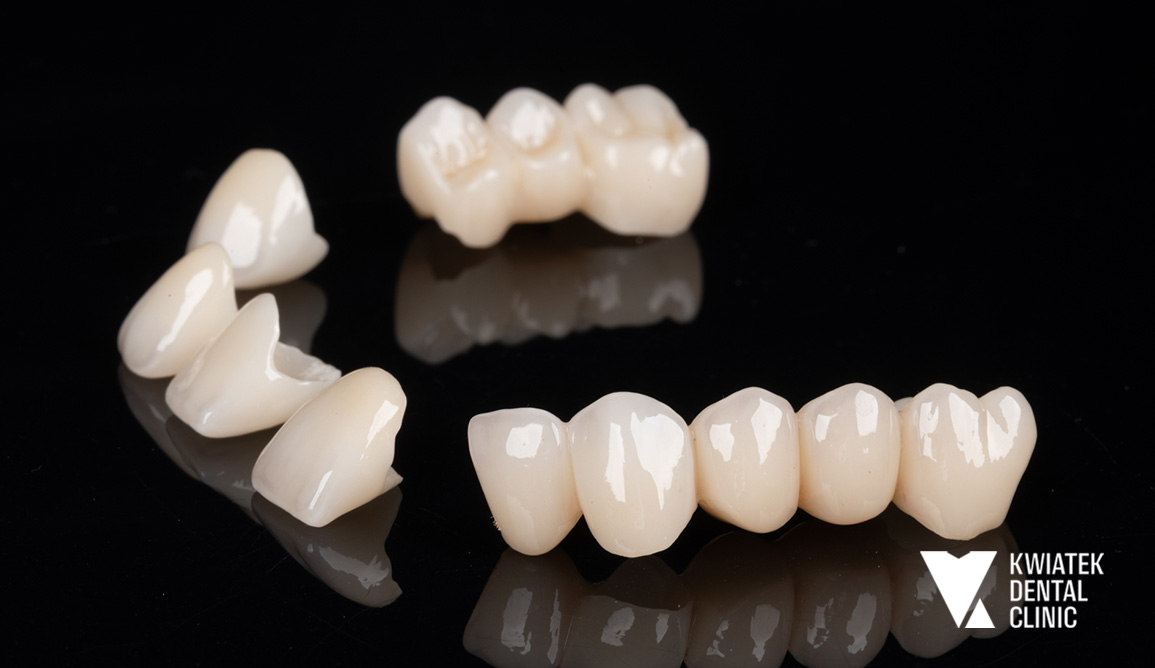

Kolejnym ważnym etapem była odbudowa brakujących zębów w odcinku bocznym żuchwy. Wykonano zabieg implantacji w pozycjach zębów 36 i 47 z użyciem systemu implantologicznego MIS C1 oraz z zastosowaniem szablonu chirurgicznego i nawigacji implantologicznej. Po zakończeniu procesu osteointegracji wykonano odbudowy protetyczne na implantach oraz korony protetyczne na zębach własnych Pacjentki. Równolegle przeprowadzono estetyczną rekonstrukcję zębów dolnych metodą flow injection, która pozwoliła na odbudowę ich kształtu i przywrócenie prawidłowych proporcji uśmiechu. Całość leczenia uzupełniono zabiegiem wybielania zębów metodą gabinetową z zastosowaniem systemu Philips Zoom.

Efektem leczenia jest kompleksowa odbudowa zdrowia jamy ustnej oraz harmonijna poprawa estetyki uśmiechu Pacjentki. Usunięto ognisko infekcji, odbudowano brakujące zęby z wykorzystaniem implantów i przywrócono prawidłową funkcję zgryzu.